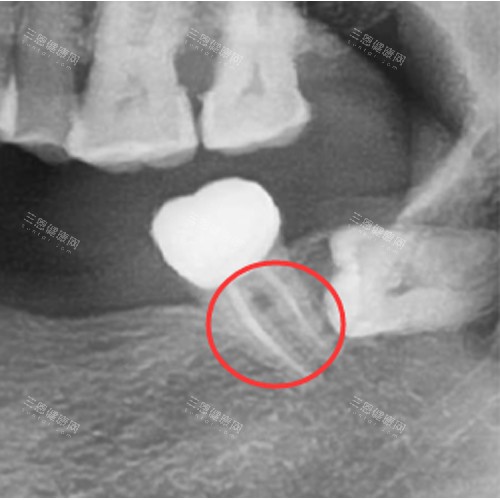

牙齿缺失的理想解决方案当属种植牙。致美口腔的种植牙服务起价4000元,这个价格通常指的是基础品牌的种植体加上普通的修复冠。如果选择国内外老牌品牌的种植系统,如瑞士或德国的某些品牌,价格会上升到6000-12000元/颗不等。

种植牙的费用构成比较复杂,通常包括术前检查、影像学检查、种植体植入手术、愈合基台、更终修复冠等多个环节。有些情况下还需要进行骨增量手术,这会产生额外费用。医院会根据患者牙槽骨条件、全身健康状况以及对美观和功能的要求,制定个性化的种植方案。

值得一提的是,致美口腔经常推出种植牙优惠活动,比如多颗种植的套餐价格会更加实惠。对于半口或全口无牙的患者,医院还提供All-on-4或All-on-6等特殊种植技术,这类治疗方案的价格需要根据具体情况评估后确定。